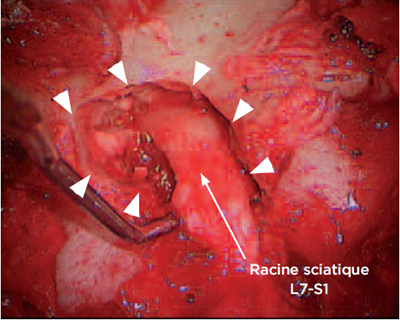

Photo 8 - Désincarcération de la racine sciatique L7-S1 par agrandissement du foramen sténosé (foraminotomie).

Cette technique dorsale ne permet pas de désincarcérer les racines du nerf sciatique qui peuvent être comprimées par le disque, latéralement, ou par des ostéophytes produits par la spondylose.

Un abord latéral est donc idéal : il permet de traiter la compression sciatique par foraminotomie (Photo 8), ainsi que la hernie discale par corpectomie latérale sur le même modèle que pour la colonne thoraco-lombaire.

Cela nécessite de pratiquer soit une section de l’ilium, soit d’aménager une ouverture au centre de la palette. L’utilisation de la vidéo-chirurgie ou de la microchirurgie devient là aussi nécessaire afin de donner au chirurgien un champ visuel de bonne qualité [3,4].